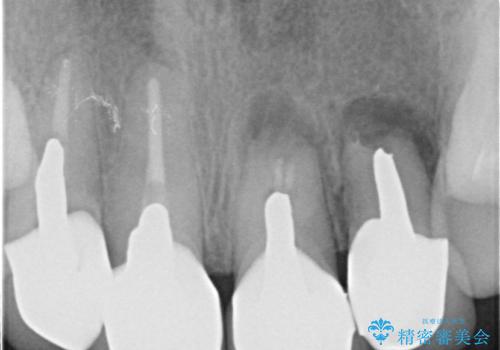

一見して問題ないように見える左側の2前歯は、セラミックを除去してみると亀裂や虫歯の再発が見られました。

抜歯時に可及的に歯肉のボリュームを保つよう骨充填材とコラーゲン製剤による填塞を行い審美的かつ機能的なブリッジとなるよう治療を進めます。

一件綺麗に見えるセラミックも適合や精度が悪いと、内部で虫歯が進行し亀裂や破折、悪臭の原因となることがあります。